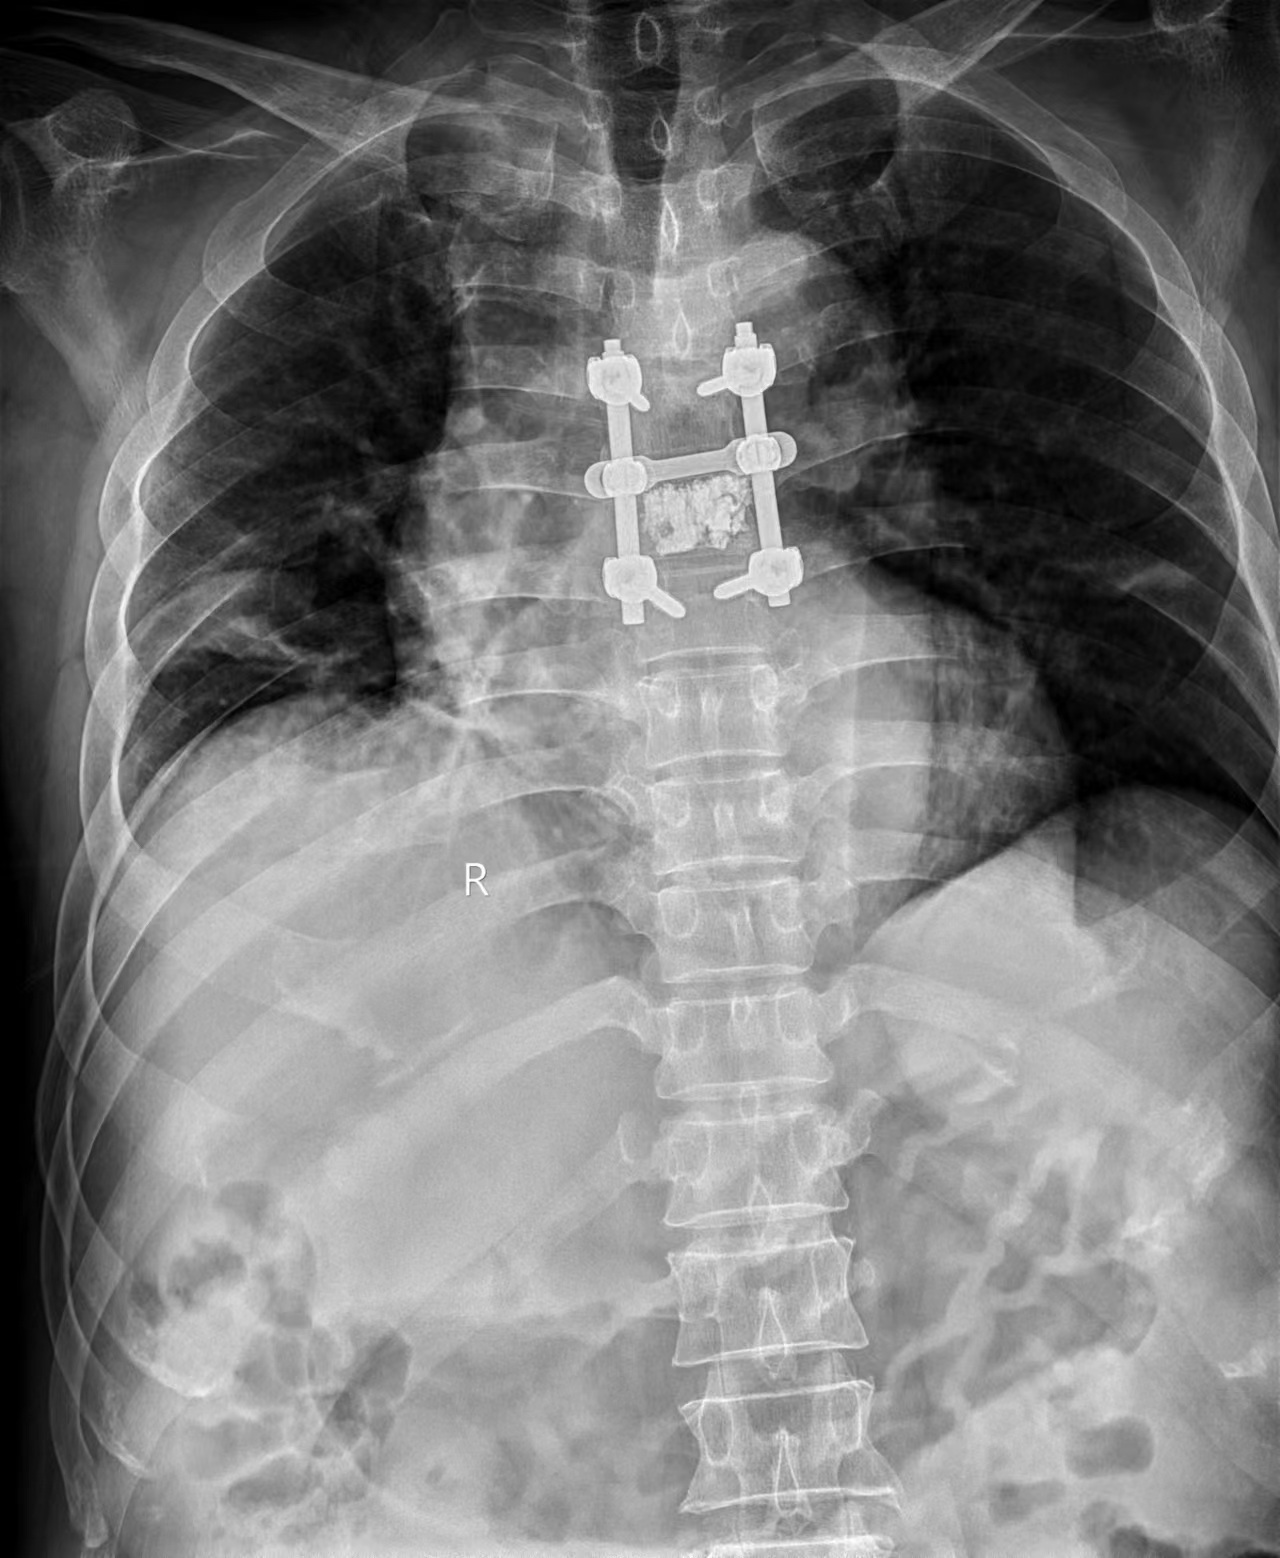

经过多方会诊与缜密分析,考虑该患者可能为一例少见的脊柱侵袭性血管瘤。血管瘤在侵蚀椎体的同时侵入椎管腔压迫脊髓,造成了患者神经功能障碍。这种血管瘤,虽冠有“瘤”名,却属于血管畸形的一种,血供异常丰富,手术只能整体一次性切除,无论是分块抑或部分切除,均可能造成术中无法控制的大出血导致灾难性后果。手术难度大,风险高。鉴于肿瘤血供丰富,对放疗可能敏感,大家一致认为,手术+放疗的方案应该是最佳选择。遂制定了胸5/7椎弓根螺钉固定+后路减压+胸6椎体灌注骨水泥+瘤体剥除+术后放疗的诊疗方案。在医院用血紧张的情况下,在家属互助献血的基础上,输血科韩梅宁主任多方协调,调用10个单位的血备用。

经过充分准备,手术于7月6日如期进行,由薛丽副主任医师麻醉,高宗强副主任医生在董军博士的帮助下,顺利完成了胸5/7椎弓根螺钉置钉、后路减压、胸6椎体灌注骨水泥等工作。在胸6椎体灌注骨水泥时,插入的套筒拔掉针芯后,鲜血就像打开的水龙头一样往外涌。当一切完成后,神经外科周乐主任医生在显微镜下进一步分离硬膜囊周围瘤体组织,见迂曲变形的血管充满了椎管腔,进一步证实了术前瘤体血供异常丰富的判断。在对脊髓进行充分减压并彻底止血后,关闭伤口,完成既定手术方案。术后第二天,患者便诉双下肢麻木症状明显减轻,如今病人下地活动1周多,无明显不适。经放疗科王宝峰教授会诊,待伤口完全愈合1个月后开始术后放疗计划。